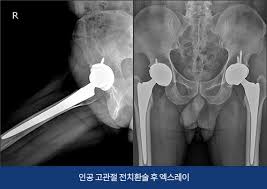

고관절 수술 후 회복 기간은 환자의 상태와 수술 방법에 따라 크게 달라집니다. 일반적으로 고관절 수술에는 두 가지 주요 유형이 있습니다. 첫째는 관절경 수술로, 최소 침습적으로 문제를 해결하는 방법입니다. 이 경우 회복 기간이 짧을 수 있습니다. 둘째는 관절 치환술로, 고관절을 인공 관절로 대체하는 수술입니다. 이 수술은 보다 복잡하며, 회복 기간이 상대적으로 더 길어진다는 특징이 있습니다.